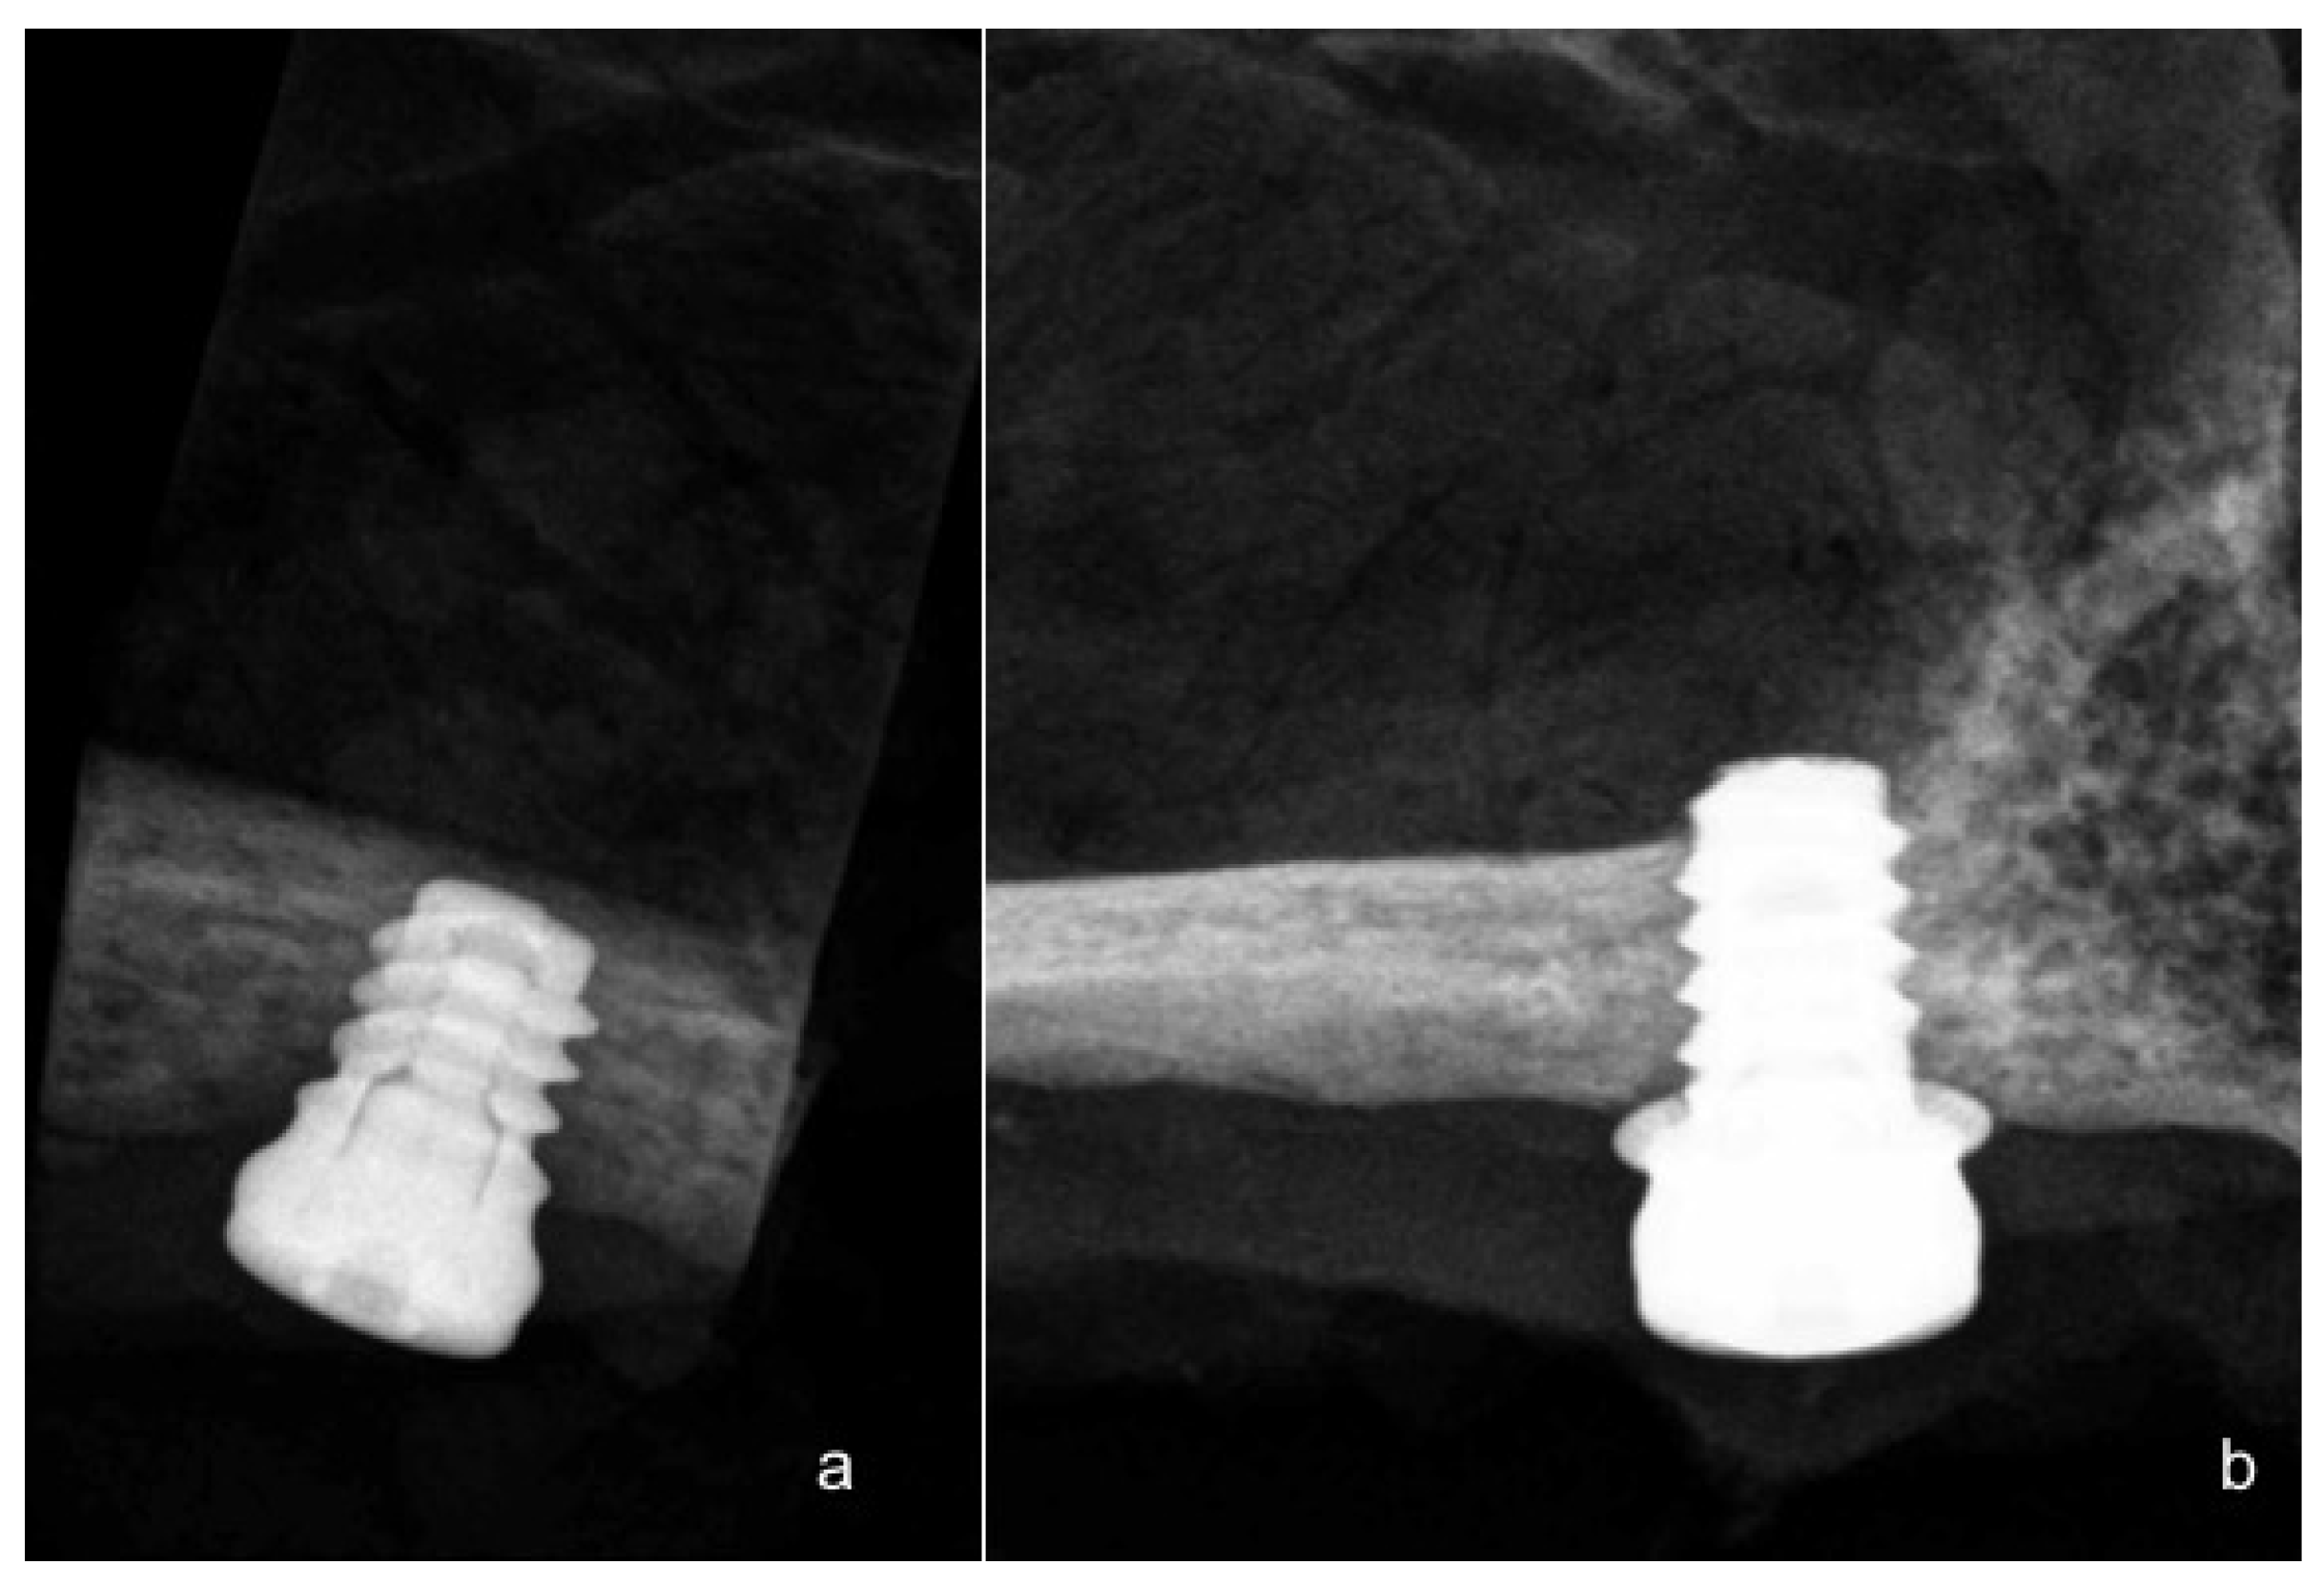

Calvo-Guirado, J.L.; Morales-Meléndez, H.; Pérez-Albacete Martínez, C.; Morales-Schwarz, D.; Kolerman, R.; Fernández-Domínguez, M.; Gehrke, S.A.; Maté-Sánchez de Val, J.E. Evaluation of the Surrounding Ring of Two Different Extra-Short Implant Designs in Crestal Bone Maintanence: A Histologic Study in Dogs. Materials 2018, 11, 1630. https://doi.org/10.3390/ma11091630